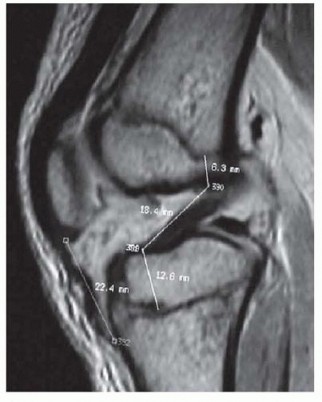

Anterior Cruciate Ligament Reconstruction in the Skeletally Immature Patient DEFINITION Skeletally immature p…